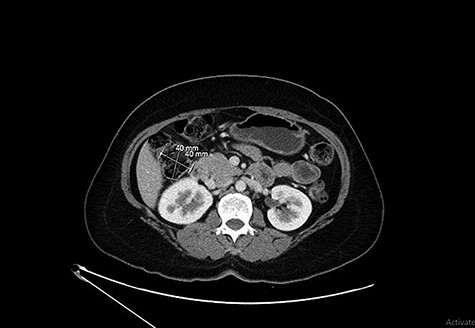

Our patient is 56-year-old female, a known case of locally advanced breast carcinoma. She was initially managed by chemotherapy followed by modified radical mastectomy then adjuvant radiotherapy and chemotherapy. The patient gave a positive family history of colon cancer; therefore, genetic testing for adenomatous polyposis coli (APC) mutation and surveillance colonoscopy were recommended by genetic counselor. The APC gene mutation came to be positive and as part of the work up for her primary disease, computed tomography (CT) scan of the abdomen performed and showed evidence of 4 cm intraluminal lesion in the ascending colon suggestive of lipoma without bowel obstruction (Fig. 1). As a result of these findings, colonoscopy was performed and it revealed a large smooth intraluminal subepithelial lesion in the ascending colon occupying one third of the lumen circumference (Fig. 2). With the use of biopsy forceps, indentation of the tumor can be seen, which is as known as “pillow sign” and once a biopsy taken, a fatty yellowish material was seen protruding from the biopsy site suggestive of lipoma (Fig. 3). Histopathological examination showed multiple fragment of normal colonic mucosa and fragments of mature adipose tissue consistent with lipoma (Fig. 4, black arrows). Clinically, the patient denied history of abdominal pain, rectal bleeding, changes in her bowel habit and intestinal obstruction symptoms. She denied any personal history of malignancy or lipoma. On physical examination, there was no evidence of any lipomas in particular her scalp, limbs or trunk. Although she has no gastrointestinal symptoms attributed to the lipoma, given that it is large in size and she is in clinical and radiological remission, we referred her for the opinion of colorectal surgery.

CT showing a lipoma arising from the wall of the ascending colon without causing obstruction.

Colonic lipomas are mostly found incidentally during colonoscopy or a CT scan. In contrast-enhanced abdominal CT scan, colonic lipoma has a uniform appearance with smooth border characteristic and fatty densitometric values between 80 and 120 Hounsfield units and that can help differentiate a benign colonic lipoma from other disease processes [7]. On the other hand, magnetic resonance imaging can detect lipomas with a signal intensity characteristic of adipose tissue on T1-weighted and fat-suppressing images [8]. Barium enema usually reveals a filling defect; however, this finding is nonspecific of colonic lipoma or any other type of colonic neoplasm. Occasionally, barium enema show ‘squeeze sign’, in which a radiolucent, spherical filling defect with well-defined margins can be shown to change size and shape in response to peristalsis [9].